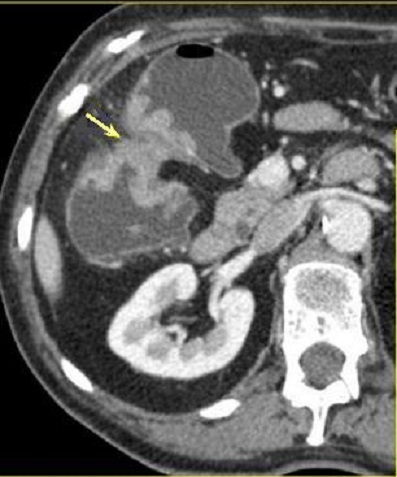

Coloscanner a

l'eau : C'est la TDM avec une opacification du

colon a l'eau tiede ( comme une lavement baryte ) a l'aide

une sonde rectale . L'exploration et les exposes represence

apres distension colique a l'eau tiede avec injection de

contrast iode hydrosoluble

par voie intraveineuse :

Image d'une polyp du colon (

fleche rouge ) . Colos scanner a eau en coupe axiale

. Cette technique peu elimine des polyps de plus de

7mm |